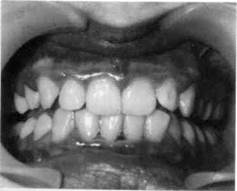

8.2.2. Пародонтит

Пародонтит — это поражение всех тканей пародонта, характеризующееся воспалением десны, разрушением зубодесневого прикрепления с образованием патологических зу-бодесневых карманов, деструкцией кости альвеолярного отростка, а при развившейся стадии — подвижностью и выпадением зубов. В практической работе часто выделяют такие стадии процесса, как активное течение пародонтита или ремиссию (рис. 8.7).

Пародонтит может быть локализованным или генерализованным. Наиболее частыми причинами локализованного пародонтита являются аномалии положения зубов и прикрепления мягких тканей к лицевому скелету, функциональная перегрузка отдельных зубов.

| Рис.8.7. Пародонтит фронтального отдела нижней челюсти. |